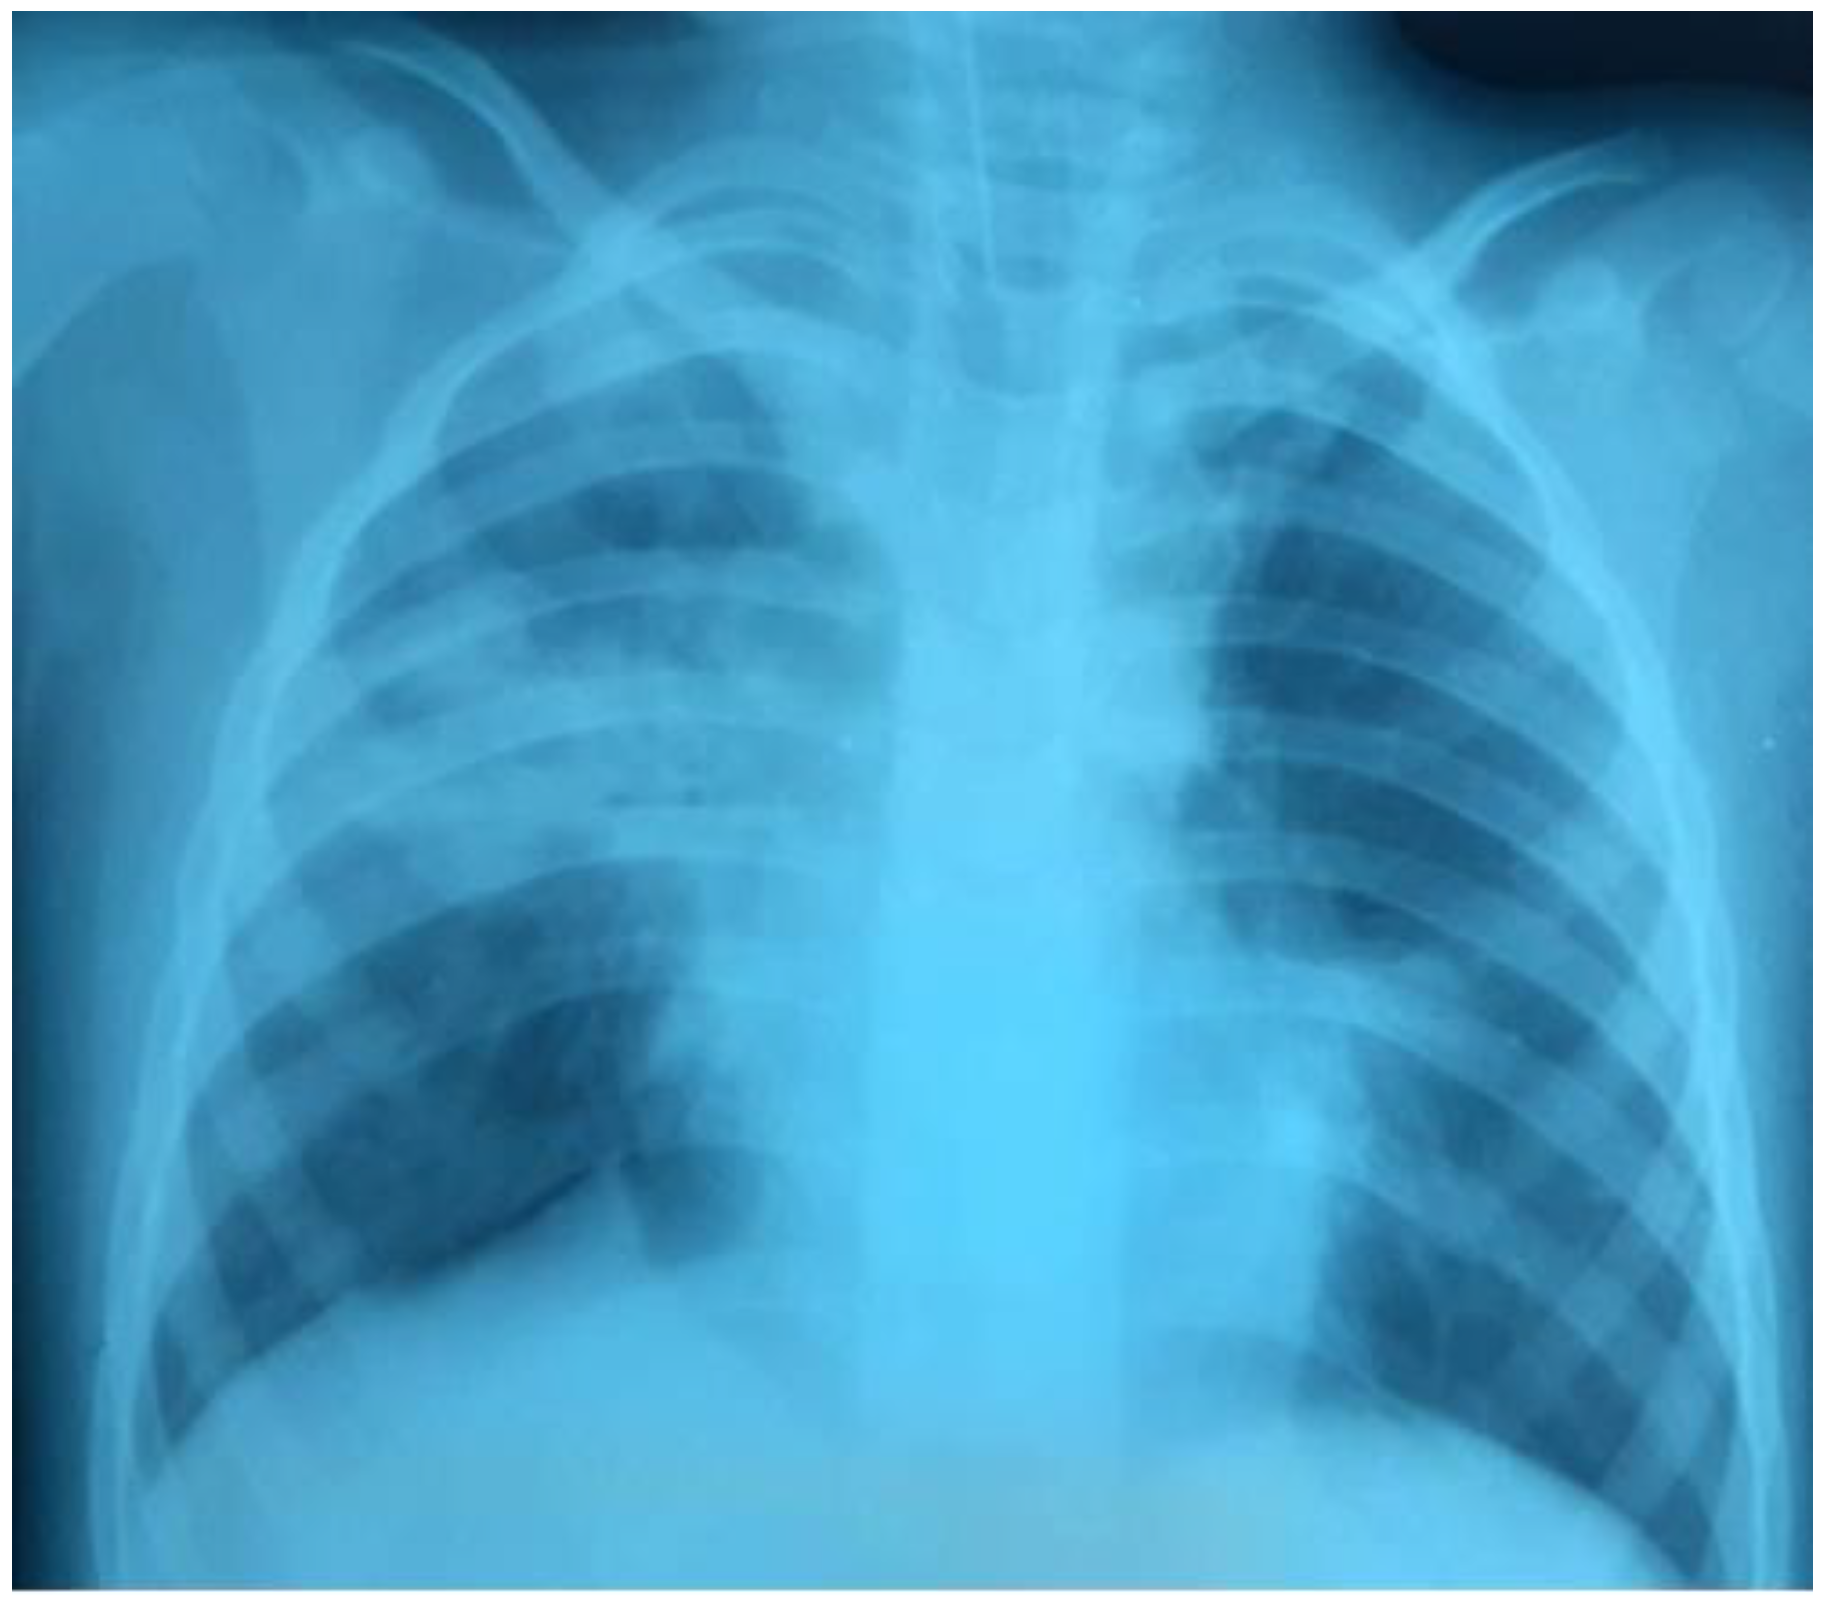

Over the next 24 hours, there was a progressive decrease in oxygenation: PaO2/FiO281, PaO2 80 mmHg, PaCO2 61 mmHg. The chest radiograph showed that the left lung was partly collapsed; there was an active air discharge through the drainage. The drainage of the left pleural cavity and the second drainage were performed (Figure 5).

Figure 5.

The left lung was partly collapsed.